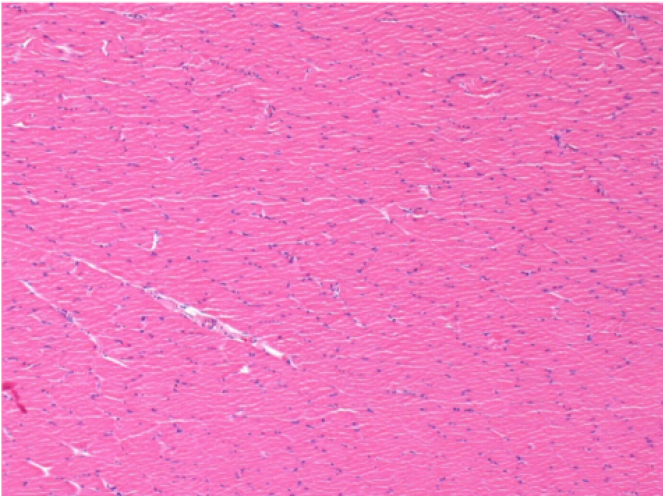

L:Pretibial-No treatment